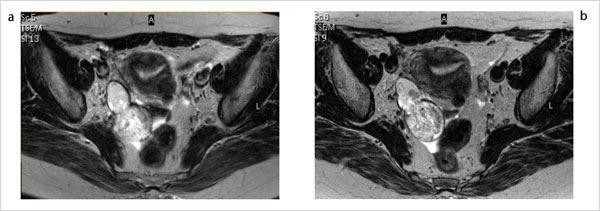

MultiTransmitによりRFパルス均一性が向上すると,局所SAR増大のリスクが軽減することから,従来の送信法で撮像した場合と比較して,安全基準による撮像時間の延長などを軽減することができる。この撮像時間の短縮効果は,空間分解能の向上へと使用することも可能となる。図6では,従来送信法により3分30秒で撮像した骨盤の画像(図6 a)と,MultiTransmitを用いて4分30秒で撮像した高分解能画像(図6 b)を比較している。1.5Tでは,SNRの限界によって撮像が難しかった高分解能撮像も,検査として現実的な時間で施行可能となることから,いよいよ3.0Tの特徴を生かした体幹部検査の実現が期待される。

図6 MultiTransmitを用いた高空間分解能画像

a:従来送信法を用いて撮像した画像。ボクセルサイズは0.82mm×0.82mm×7mmで,撮像時間は3分30秒である。

b:MultiTransmitを用いて撮像した画像。ボクセルサイズは0.58mm×0.58mm×3mmで,撮像時間は4分30秒である。

(画像ご提供:東海大学病院様)